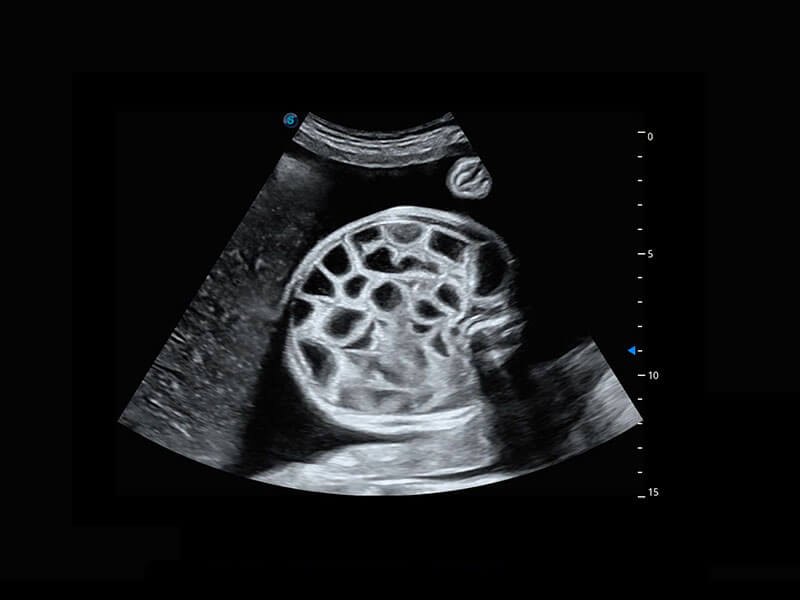

P60在胎儿早孕期超声筛查中为您带来优异的图像质量。

高分辨率容积成像-早孕胎儿